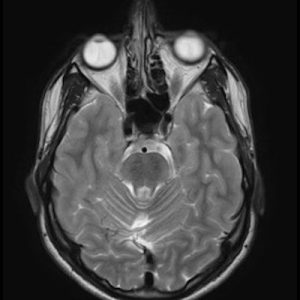

📣📣📣Haftanın ödüllü olgu sorusu yayınlandı.

Yanıtlarınızı www.tnrd.org.tr adresinden bekliyoruz.